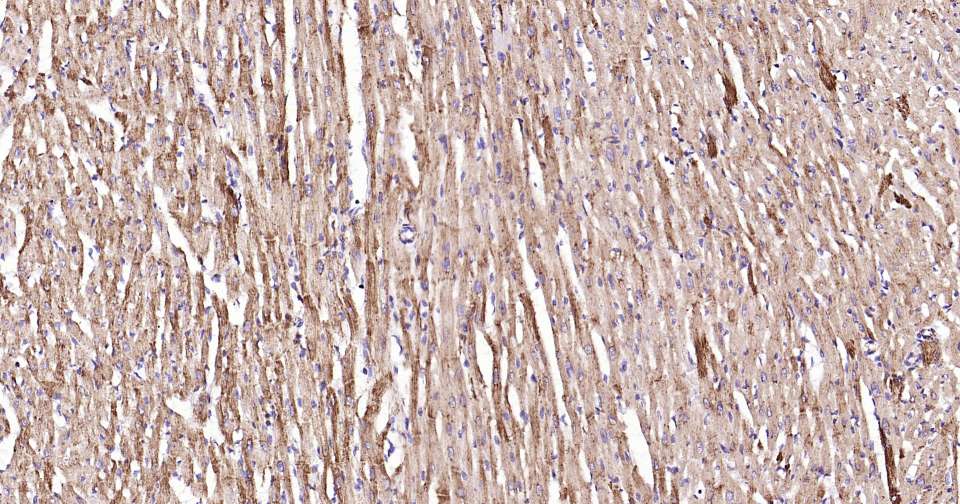

Immunohistochemical analysis of paraffin embedded mouse heart tissue slide using IHC0317 (HSP60 Kit).

Immunohistochemical analysis of paraffin embedded human heart tissue slide using IHC0317 (HSP60 Kit).

Immunohistochemical analysis of paraffin embedded rat heart tissue slide using IHC0317 (HSP60 Kit).